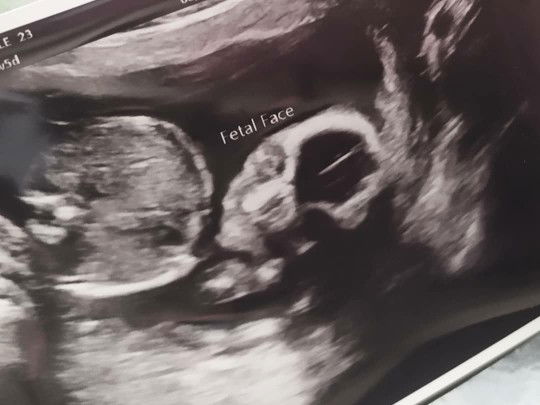

Excited to see my princess